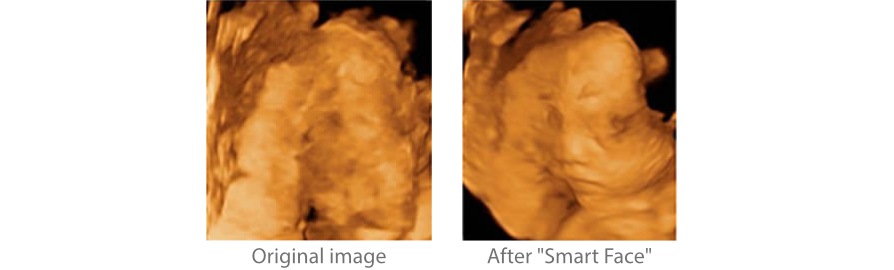

Smart Face

Nowy aparat Z60 zapewnia szybk? i inteligentn? optymalizacj? obrazu twarzy p?odu po jednym dotkni?ciu. Natychmiast usuwa okluzje w danych obj?to?ciowych, eliminuje niepo??dane szumy, generuj?c optymalny widok twarzy p?odu z minimalnym wysi?kiem.